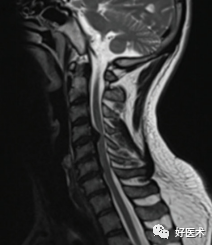

图示:谭军教授团队提出的颈椎间盘突出的形态学分型示意图